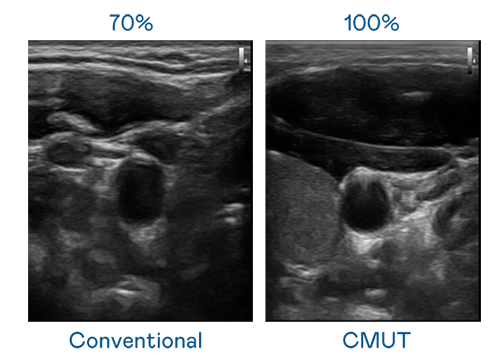

AUO utilizes TFT (Array) to expand cutting-edge sensing technology and develop various sensor component products. High-resolution CMUT components with stable quality and mass production capabilities can be used to produce high-resolution ultrasound probes and patch-type probes for administering accurate measurement and physiological monitoring over extended periods on patients.